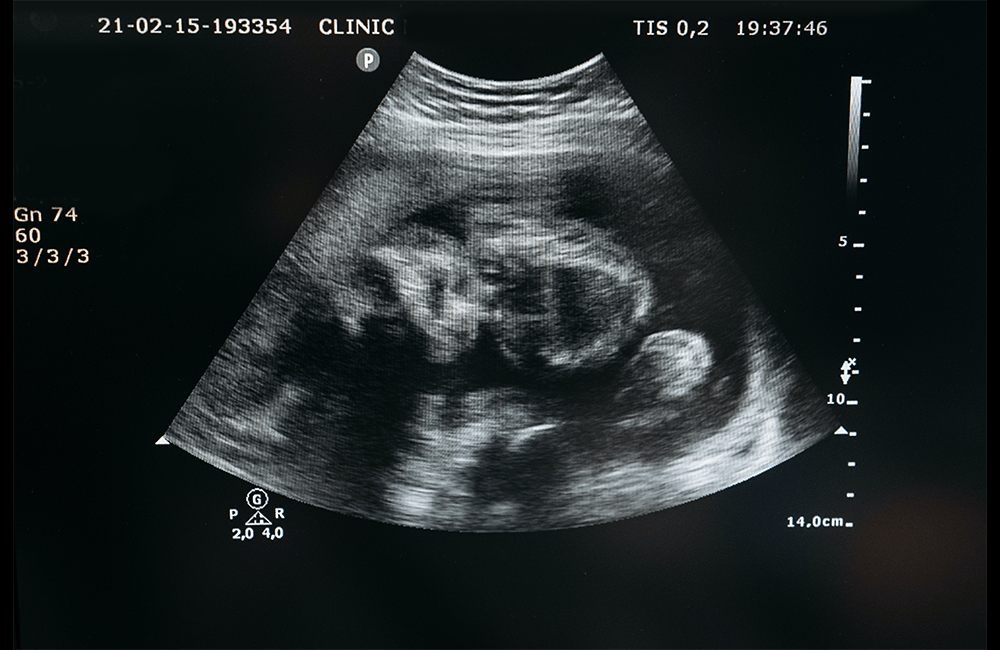

Gracias a los avances tecnológicos, la ciencia nos afirma que ya entre los dieciocho y veinticuatro días se puede detectar con un ultrasonido el latido del corazón.